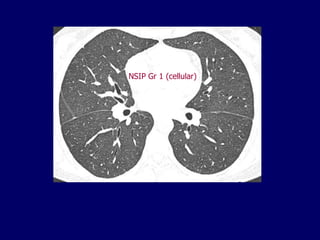

NSIP Gr 3 (fibrotic)

NSIP Gr 1 (cellular)

NSIP Gr 3(fibrotic)

• 93.

NSIP Gr 1(cellular)